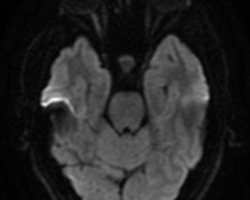

- IRM cérébro-orbitaire : névrite OD, normal à gauche

- IRM cérébro-orbitaire : présence de quelques hypersignaux FLAIR de la substance blanche sous corticale au niveau frontal bilatéral peu spécifiques. Absence de rehaussement pathologique au niveau parenchymateux ou méningé après injection de sel de Gadolinium. Les structures médianes sont en place. Pas d’anomalie de la filière ventriculaire. Aspect perméable des veines intracrâniennes après injection de sel de Gadolinium. Aspect épaissi, en hypersignal T2, et rehaussé du nerf optique droit dans sa portion intra orbitaire compatible avec une névrite.

Conclusion : Névrite orbitaire droite. Quelques hypersignaux FLAIR de la substance blanche au niveau sus-tentoriel frontal bilatéral peu spécifiques. (Oriente vers une ancienne poussée de névrite à gauche)